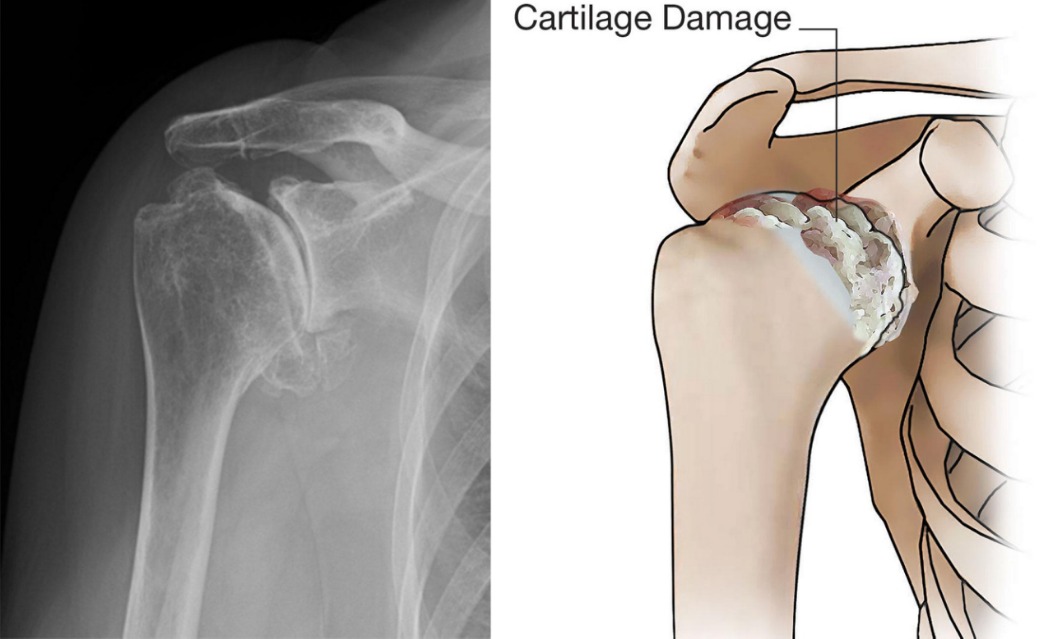

- Osteoarthritis Also called “wear-and-tear” arthritis Caused by gradual cartilage degeneration More common after age 50 Often affects the AC joint, but glenohumeral arthritis causes more symptoms

- X-rays

- Joint space narrowing

- Bone spurs

- Joint deformity